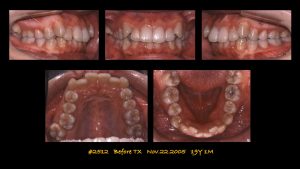

症例 1:日本矯正歯科学会専門医試験に合格した症例

症例 2:World Board of Lingual Orthodonticsに合格した症例

症例 3:日本矯正歯科学会専門医試験に合格した症例

症例4:European Board of Orthodonticsに合格した症例